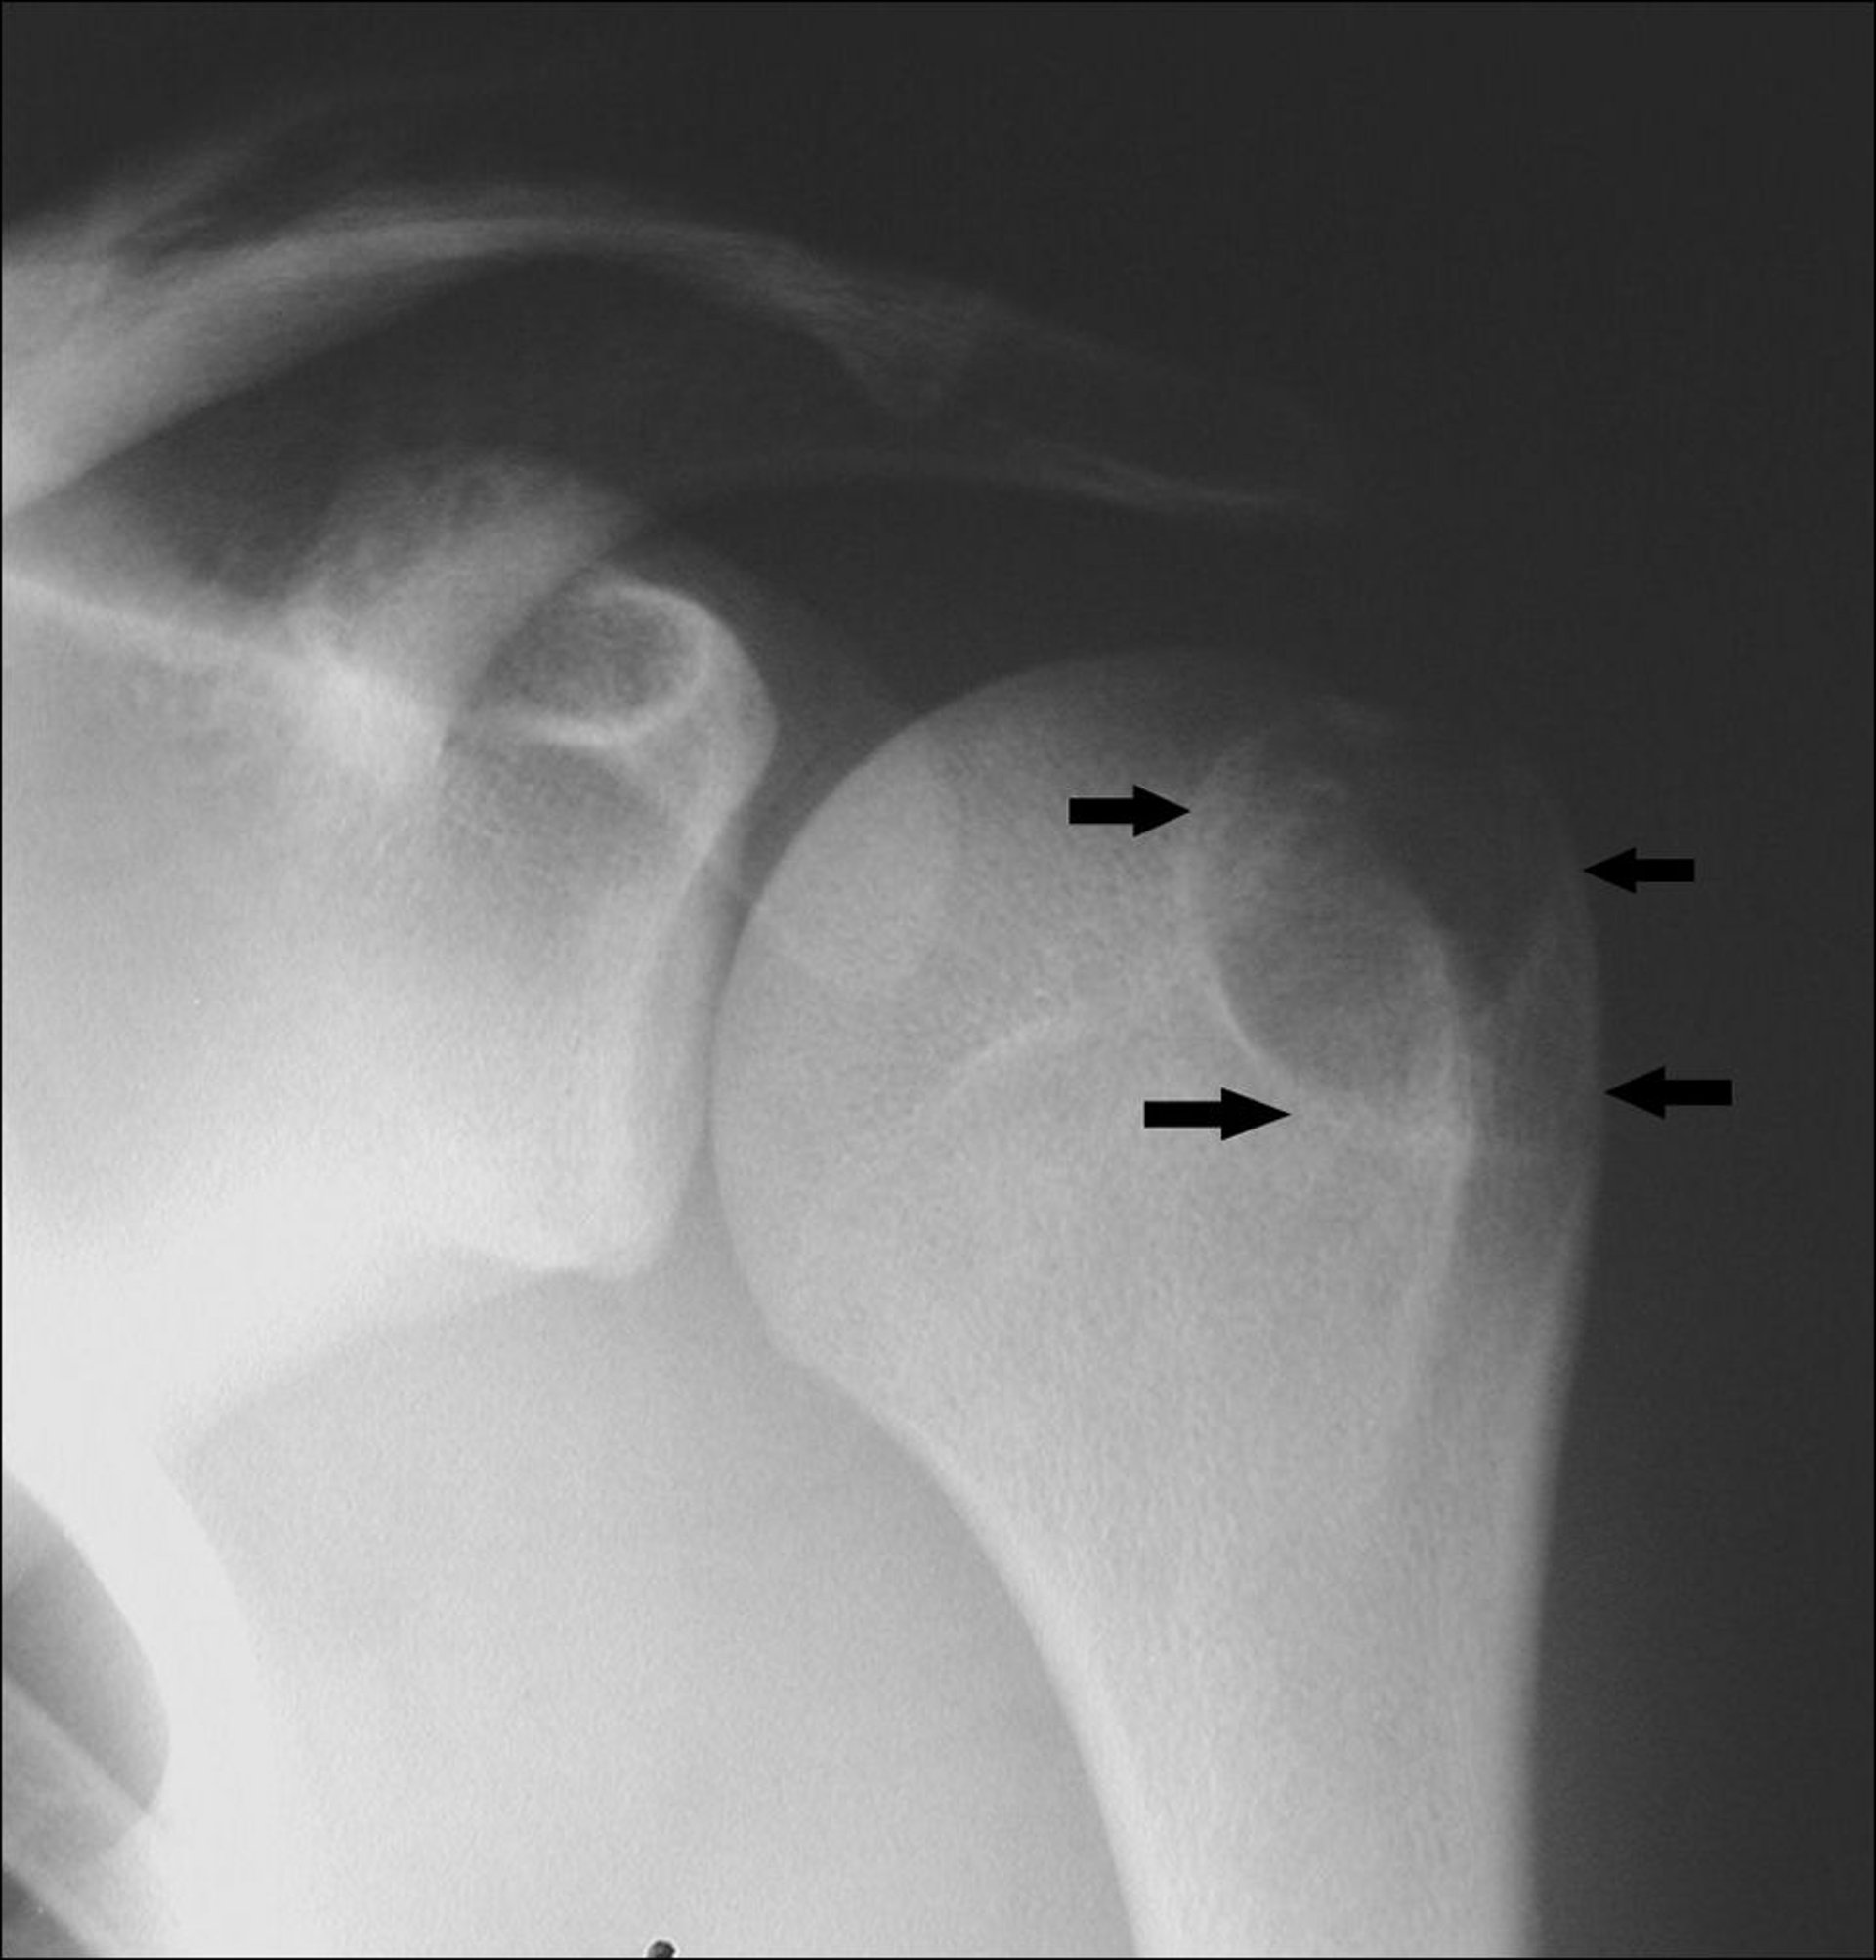

Questa radiografia della spalla mostra un condroblastoma nell'omero a livello dell'apofisi del tubercolo maggiore (frecce).

Image courtesy of Michael J. Joyce, MD, and Hakan Ilaslan, MD.